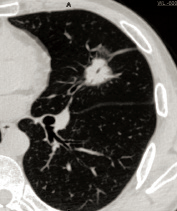

A CT scan machine plays a pivotal role in cancer detection and evaluation. Doctors often use CT scan machines to detect tumors, determine whether cancer has spread (metastasized) to other parts of the body, and assess their size.

Tumor Detection

CT scan machines can spot abnormal growths (tumors) in organs like the lungs, liver, pancreas, and colon. For example, a low-dose CT scan is often used for lung cancer screening in high risk groups (e.g., long-term smokers), as it can detect small nodules that might be cancerous.

Cancer Staging

Once a tumor is detected, a CT scan is used to evaluate the extent of cancer metastasis. By generating detailed cross-sectional images of the body, CT scan machines allow doctors to identify whether the cancer has invaded adjacent tissues, lymph nodes, or distant organs — information critical for accurate cancer staging. This precise mapping of affected regions enables clinicians to develop an optimized treatment strategy, which may include surgery, radiation therapy, or chemotherapy.

Treatment Effectiveness Monitoring

CT scan machines deliver clear, detailed images that enable physicians to monitor changes in a tumor’s size and structure over time. By comparing scans taken before, during, and after treatment, doctors can evaluate whether the tumor is shrinking, stable, or growing — offering critical insight into the effectiveness of chemotherapy, radiation, or targeted therapies. These scans can also detect new metastatic lesions, allowing for timely adjustments to the treatment plan when needed.